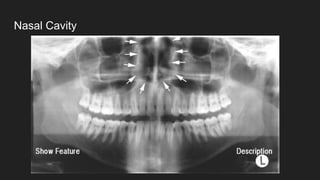

● Nasal cavity

Nasal Cavity